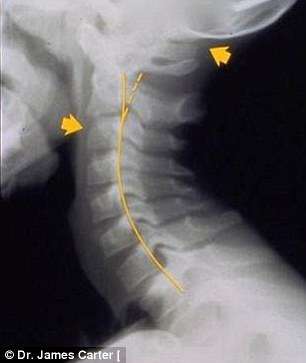

A condição, chamada de ‘text neck’ (‘Pescoço de mensagem’, em português), é observada em pessoas que sentam com suas cabeças a frente do corpo para interagirem com os seus smartphones ou tablets durante algumas horas.

Em geral, o peso da cabeça humana varia entre 4,5 kg e 55, kg, e a projeção do pescoço para frente faz com que o peso seja mais difícil de suportar, o que aumenta a probabilidade do surgimento de dores musculares e o encurvamento da espinha dorsal.